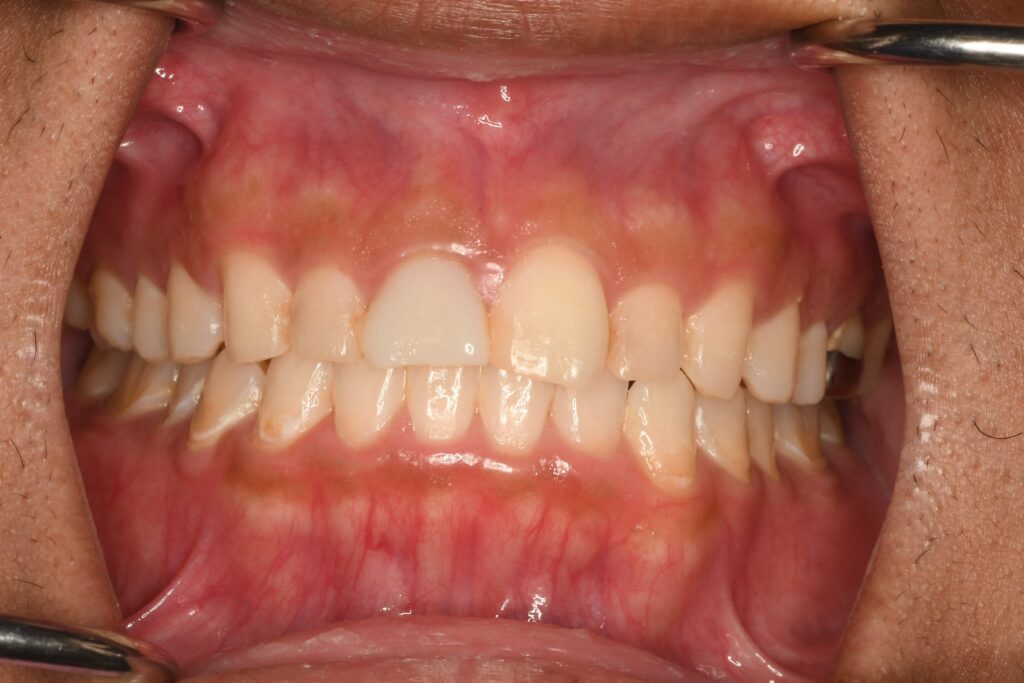

写真が斜めでごめんなさい。矯正治療後の写真です。

最初がこんな感じでしたから随分整っていましょね。これからは良くなった状態を保つために一緒に頑張っていきましょう。